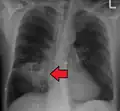

Les abcès pulmonaires sont souvent d'un seul côté et concernent les segments postérieurs des lobes supérieurs et les segments apicaux des lobes inférieurs, car ces zones dépendent de la gravité en position couchée. La présence de niveaux air-fluide implique une rupture dans l'arbre bronchique ou, rarement, la croissance d'un organisme gazogène.[réf. nécessaire]

Abcès pulmonaire sur CXR